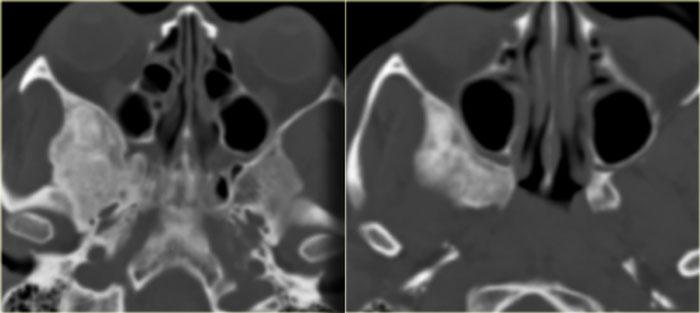

Hình ảnh bên trái của một bệnh nhân khác được đọc là có u mô mềm (mũi tên vàng) ở phía trước xương thái dương.

Đây là các hình ảnh CT cắt ngang tương ứng cho thấy hình ảnh loạn sản xơ điển hình của cánh xương bướm.

Chẩn đoán phân biệt cần đặt ra là u màng não (meningioma).